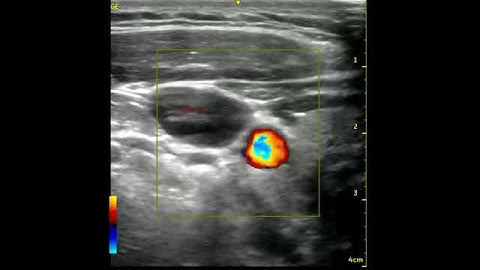

IJV Valsalva